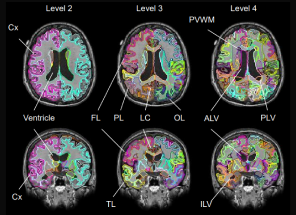

(AI認知症将来リスク予測検査)脳の一部(海馬など)のみならず、脳全体の状態を把握することで、膨大なデータベースと照合し高精度の解析を実現。脳各部位の体積の将来変化を予測することで、これまでの解析以上に正確な脳状態を確認できます。

(海馬体積・認知症スコア)Brain Life Imaging®(海馬体積年齢・認知症スコア)では、簡単な認知機能テストと脳MRIをAIで解析し、「海馬」領域の体積を測定・可視化し、認知機能の早期対策へ導くAIプログラムです。